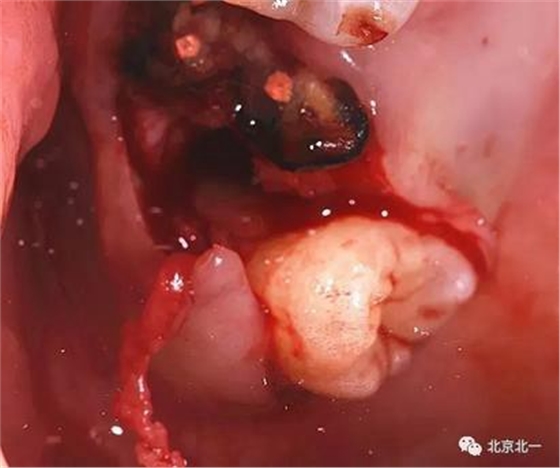

圖六:牙冠完整被挺松。

360截圖20170124104411590.jpg